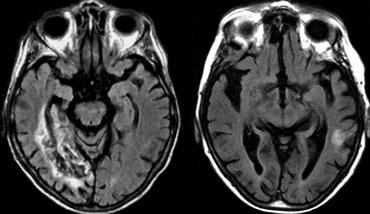

Bên trái là hình ảnh MRI của nhồi máu PICA bên trái.

Trong các trường hợp nhồi máu một bên, luôn có sự phân định rõ ràng tại đường giữa do các nhánh nhung mao trên không vượt qua đường giữa mà đi theo hướng dọc (sagittal).

Sự phân định rõ ràng này có thể không biểu hiện cho đến giai đoạn muộn của nhồi máu.

Trong giai đoạn sớm, phù nề có thể vượt qua đường giữa và gây khó khăn cho chẩn đoán.

Nhồi máu ở mức cầu não thường có vị trí cạnh đường giữa và được phân định rõ ràng do các nhánh của động mạch nền đi theo hướng dọc và không vượt qua đường giữa.